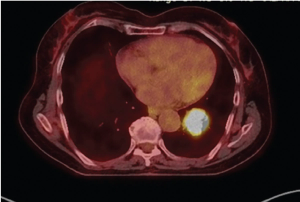

Read about a woman with well-differentiated atypical carcinoid who experienced a 21% regression in primary tumor size after 12 months on neoadjuvant capecitabine and temozolomide.